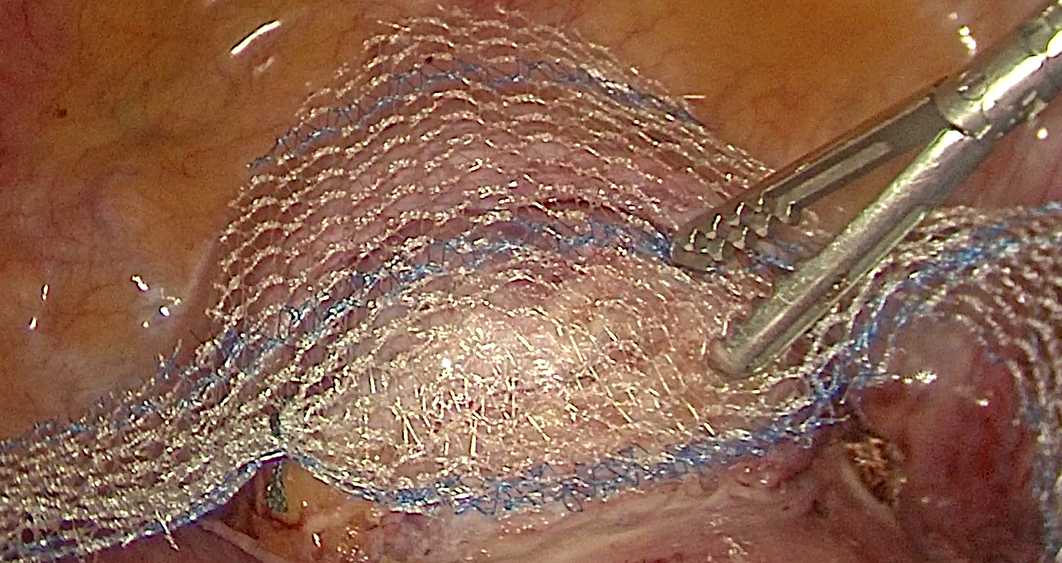

在家人陪伴下,王女士来到仙桃市第一人民医院妇科寻求帮助。科主任卢余莉为她进行了详细的专科检查与综合评估,诊断其为子宫脱垂II度、阴道前壁脱垂II度,并伴有I型压力性尿失禁。卢余莉主任充分理解患者与家属的顾虑,结合病情实际与患者意愿,为其制定了个体化手术方案,决定实施腹腔镜下侧腹壁悬吊术。

该手术时间短、创面小,在成功保留子宫的同时,有效重建了盆底的支撑结构。术后,王女士恢复情况良好,脱垂症状得到显著改善,排尿功能明显提升,且未出现相关并发症。困扰她多年的问题终于得以解决,生活质量获得了实实在在的提高。